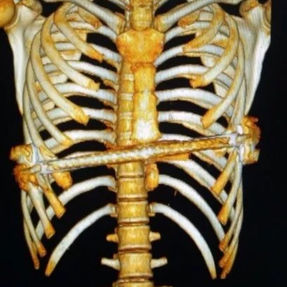

The patient’s anterior chest wall exhibits a prominent depression deformity,characterized by a horizontal groove that affects both sides of the anterior chest wall. There is a surgical scar along the midline and one on the left side, with two scars visible on the right side of the chest wall. A 4x4 cm mass is located on the left chest wall, characterized by darkened skin and noticeable fluctuation upon palpation. The mass extends deep into the intercostal space. Mild scoliosis is also observed. The patient was ultimately diagnosed with grooved chest.

2. Improper bar Placement and Positioning: Preoperative imaging reveals that the bar was positioned along the upper edge of the groove-like depression and was placed at an angle.For optimal support and effective correction of the depressed bony structure, the bar should have been positioned at the base of the depression.

3. Insufficient Number of Bars: In adult patients, the larger chest wall depression and increased bone density generally necessitate the use of at least two bars during corrective surgeries to ensure adequate support and achieve the desired outcome. However, only one bar was used in the patient’s initial surgery, which was insufficient to effectively correct the depression.